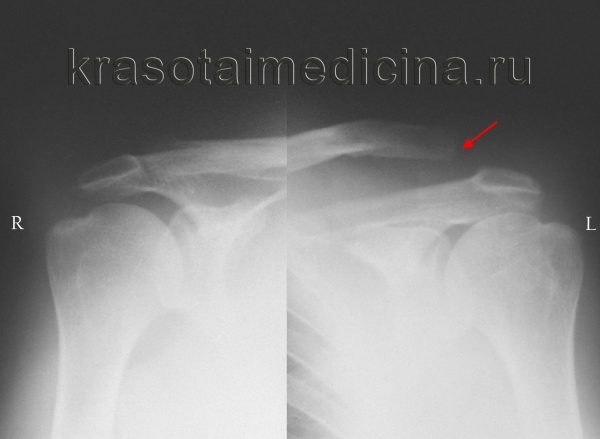

• Рентгенологическое исследование. Для подтверждения диагноза выполняется рентген акромиально-ключичного сустава или грудино-ключичного сочленения. В случае неполных вывихов может потребоваться сравнительная рентгенограмма обеих сочленений, иногда с функциональной нагрузкой (например, пациент держит небольшой груз).

Рентгенография акромиально-ключичных суставов показывает вывих акромиального конца левой ключицы (справа — норма для сравнения).